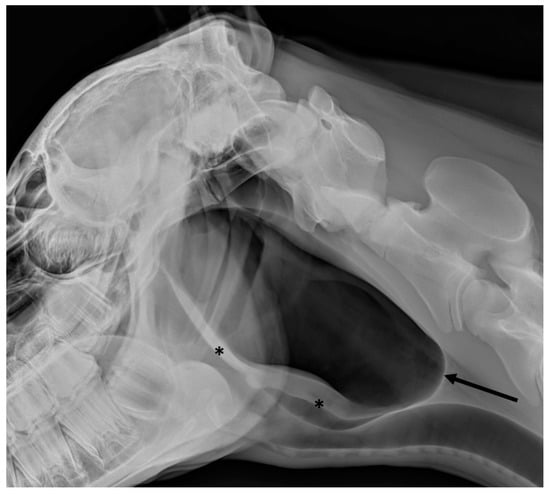

2.1. Radiography

3.2. Guttural Pouch Tympany

3.3. Guttural Pouch Hemorrhage